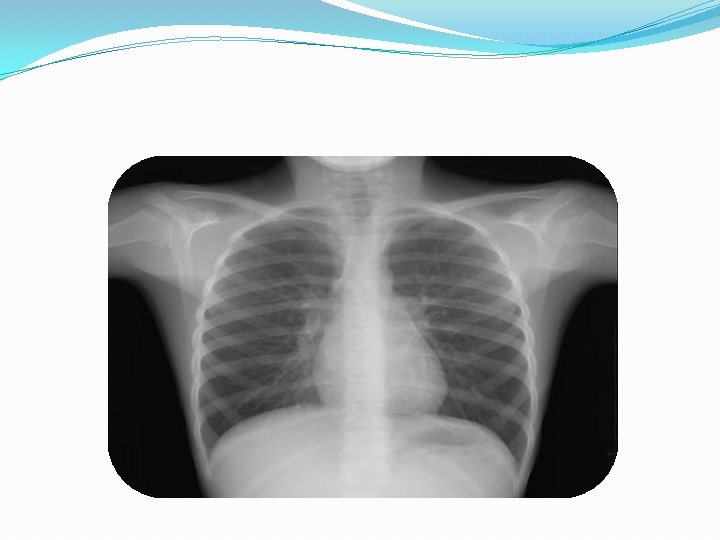

TORAX �Se examina con el paciente sentado, con el torso desnudo. � Un paciente en mal estado se evalúa acostado, por partes, cambiándolo de posición.

EXAMEN � Se debe examinar de manera comparativa, con el hemitorax contralateral. Desnudo, sentado. � Observando la expansibilidad de la caja torácica y los movimientos respiratorios.

EL EXAMEN DEL TORAX �Siempre se hace comparatívo con el lado contralateral, siguiendo los cuatro aspectos del exámen físico (inspección, palpación, percusión y auscultación)